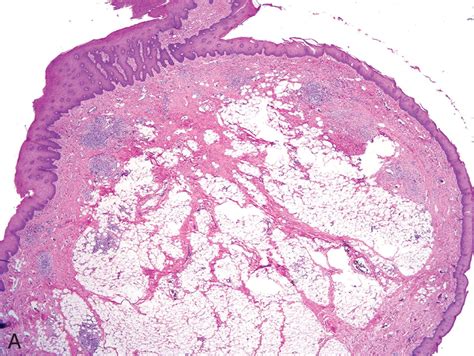

• Fibrovascular Polyps: These are rare, benign lesions that consist of fibrous, adipose, and vascular tissue. They can sometimes grow quite large and cause obstructive symptoms.

• Leiomyomas: While technically tumors of the smooth muscle, they are often grouped into the discussion of esophageal masses. They are almost always benign.